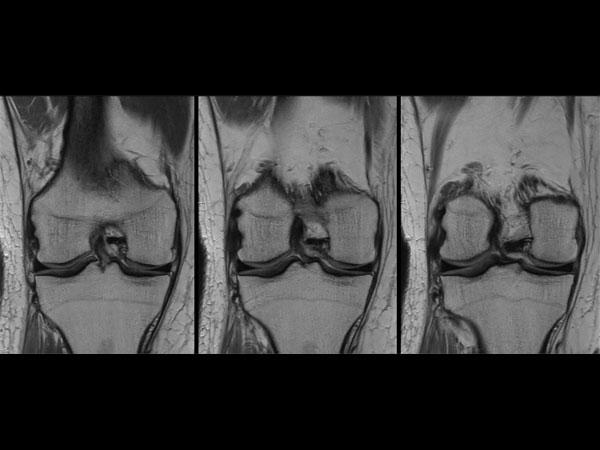

Knee imaging